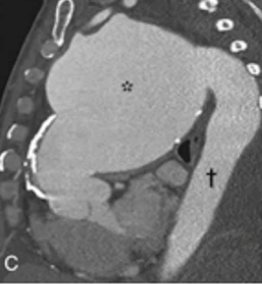

Treponema Pallidum - Gram negative spirochete which causes syphillis. Grown in special medium, slow, low oxygen conditions. Treated with penicillin. (Aortic aneurism and regurgitation)